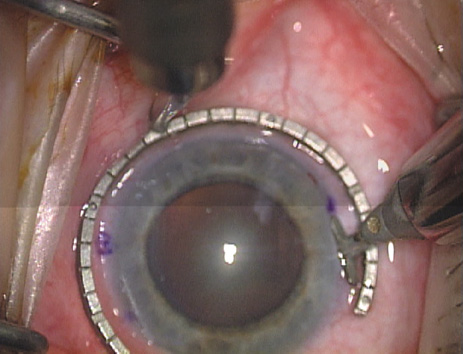

The extent of arc to be incised may be demarcated in several different ways. Our preferred method makes use of a modified Fine-Thornton fixation ring (Nichamin Fixation Ring and Gauge; Mastel Precision, Storz, Rhein Medical). This instrument serves to fixate and position the globe in order to optimize incision placement, as well as to delineate the extent of arc to be incised. One visually extrapolates from the limbus to marks on the surface of the ring. Each incremental mark is 10 degrees apart, and bold hash marks (180 degrees) opposite to each other serve to align and center the incision over the steep meridian. This approach obviates the need to ink and physically mark the cornea. If one desires, particularly when first gaining experience with LRIs, a two-cut RK marker may be used to place ink marks upon the cornea to show the exact extent of arc that is to be incised, in conjunction with the fixation ring/gauge (Fig. 4). Alternatively, various press-on markers are available, such as those made by Rhein Medical (Dell-Nichamin Marker, Nichamin-Kershner Marker, or the Ruminson Marker) (Fig. 5). ASICO and other instrument companies offer a full line of dedicated markers, rings, and blades for performing LRIs.

Fig. 9. The broad hash marks of the fixation ring/gauge are centered over the 75-degree meridian, using the 6:00 limbal mark for orientation. Alternatively, a Mendez gauge may be used. (Reprinted from Hardten DR, Lindstrom RL, Davis EA. Phakic Intraocular Lenses: Principles and Practice. Thorofare, NJ: SLACK Incorporated, 2004, with permission.)

Fig. 12. In this left eye, the steep meridian is at the 120-degree axis and has been delineated by opposing limbal marks. The upper left hand ink mark represents the 6:00 position for orientation. (Reprinted from Hardten DR, Lindstrom RL, Davis EA. Phakic Intraocular Lenses: Principles and Practice. Thorofare, NJ: SLACK Incorporated, 2004, with permission.)

Fig. 21. The broad hash marks of the fixation ring are centered just off of the 6:00 limbal orientation mark, over the 85 degree meridian in this left eye. The two cut RK marker is positioned at one extent of the LRI, just under 30 degrees from the central steep meridian and the cornea is marked.